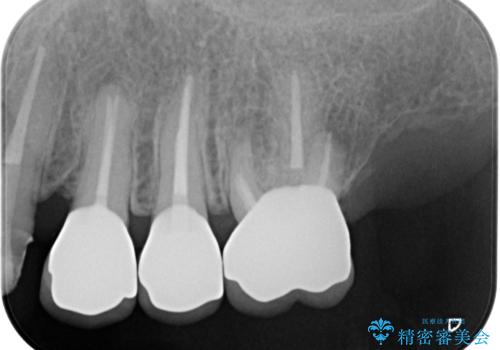

- 精密根管治療

- 2012~2025年6月

- 000歯